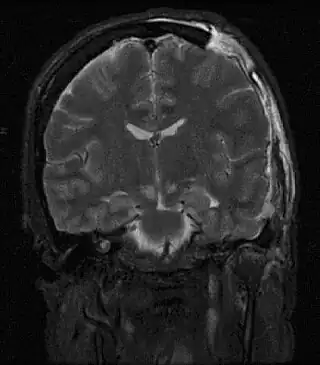

Resonancia magnética mostrando lesión causada por hernia cerebral. | ||